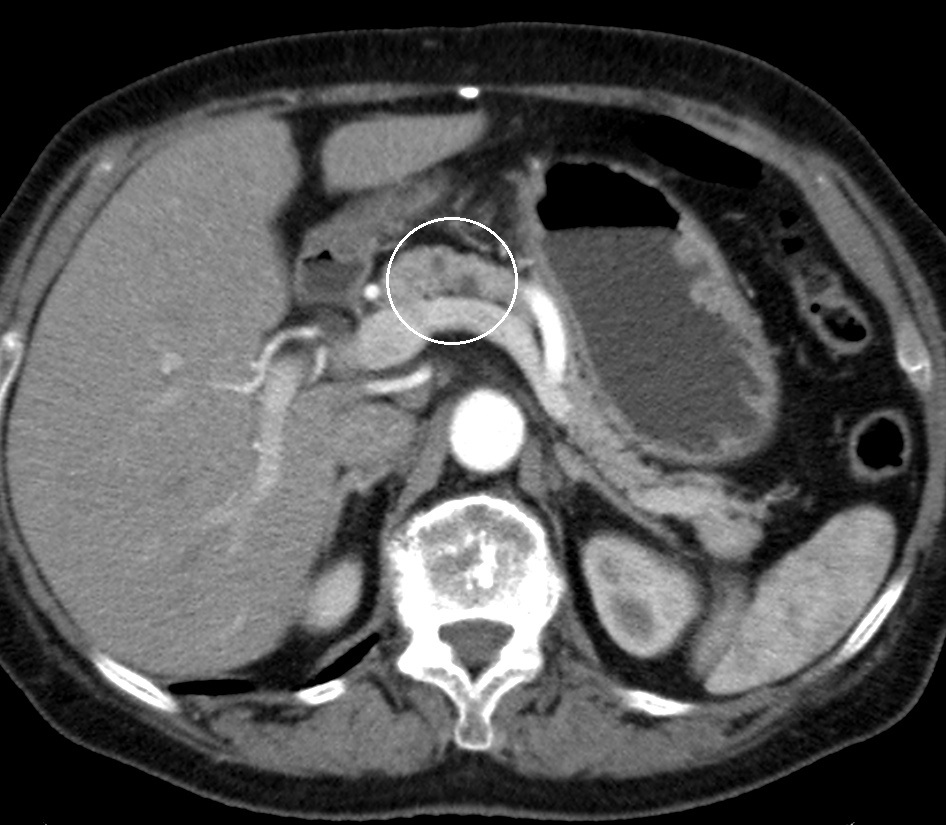

КТ ретроперитонеального фиброза: Изображения и диагностика